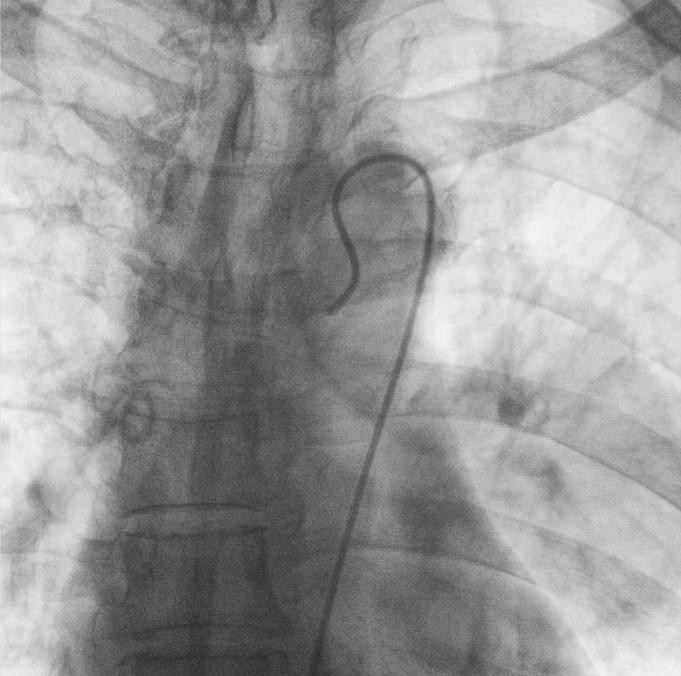

在普愛醫療移動式平板介入中C影像的引導下,醫生為患者實施雙側支氣管動脈栓塞+化療灌注術。

普愛醫療移動式平板介入中C

作為國內C形臂市場占有率連續十余年當先的民族品牌,普愛醫療推出的PLX7100A移動式平板介入中C,憑借體積小、劑量低、圖像清晰、操作便捷等特點,在廣大基層醫院腫瘤介入科以及三甲醫院??平槿氆@得了越來越多醫院和專家的認可。